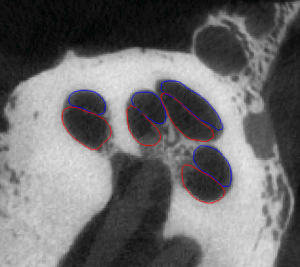

Segmentation of intracochlear structures (Scala Tympani, Scala Vestibuli and Media, and Modiolus) would aid surgical guidance and post-surgery analysis of electrode positioning, which could help improve placement outcomes and lead to better hearing outcomes. However, intracochlear structures are too small to be seen in conventional in vivo imaging, thus traditional segmentation techniques are inadequate. In this work, we circumvent this problem by creating a weighted active shape model with micro CT (μCT) scans of the cochlea acquired ex-vivo (see video of Scala Tympani=Red, Scala Vestibuli=Blue, and Modiolus=green manually segmented in μCT). We then use this model to segment conventional CT scans. The model is fit to the partial information available in the conventional scans and used to estimate the position of structures not visible in these images. Quantitative evaluation of our method, made possible by the set of μCTs, results in Dice similarity coefficients averaging 0.77 and surface errors of 0.15 mm. A video of the shapes in the model is shown here (Red=ST, Blue=SV/SM, Green=Promontory).